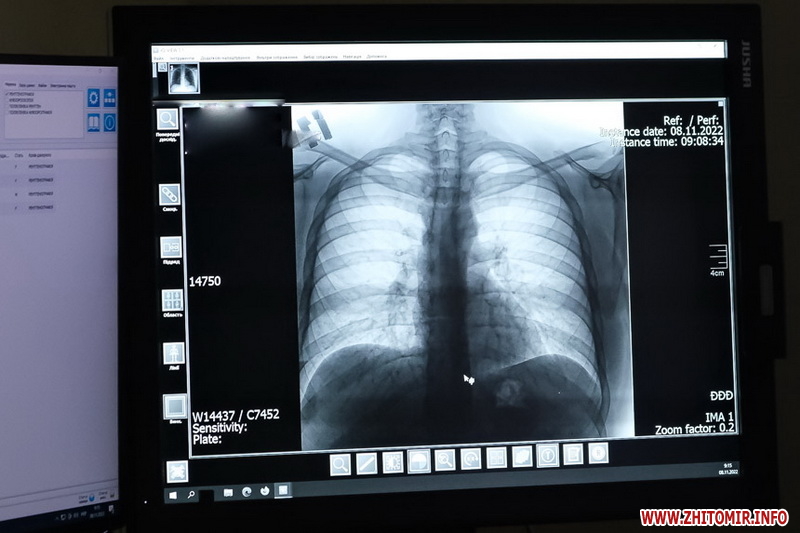

«Рентгенологія - важлива частина дослідного процесу. Ми є первинною ланкою досліджень, на відміну від КТ та МРТ. В обов’язки нашого кабінету входить рентген-обстеження пацієнтів за направленням від їх лікаря. Обстежуємо легені, кістки, суглоби і деколи навіть живіт. Ми можемо побачити пневмонії, метастази, туберкульоз, подивитися ушкодження суглобових поверхонь, оглянути кістки після травм чи аварій тощо. Також можемо за допомогою барію побачити, чи є у пацієнта проблеми з прохідністю шлункового вмісту. Можемо побачити чи є гайморит тощо. Наша система цифрова і новітня. Ми вже не працюємо з плівками. Цифра - це дуже добре, бо дозволяє одразу побачити знімок, перевірити все і швидко повідомити пацієнта та його лікаря», - розповідає Богдан Кузєв.

Знімки зараз рідше друкують на плівці або папері, частіше зберігають у цифровому форматі.

Знімки робить лаборант, тоді по системі лікарі отримують їх на комп’ютер в ординаторську. На екрані вони розглядають їх у найдрібніших деталях, наближають, змінюють контраст, порівнюють в динаміці з архівами, дивляться у різних проєкціях та роблять висновок. Діагноз і лікування на основі цих досліджень вже визначає лікар, який направляв пацієнта на рентген.